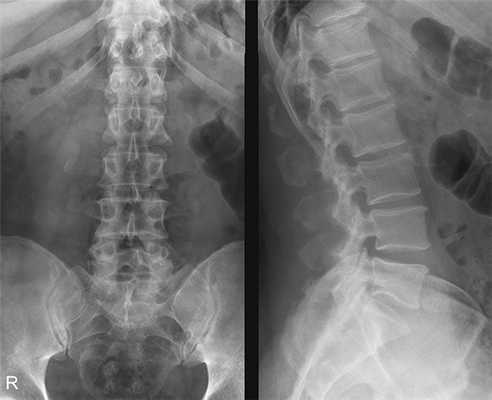

РИСУНОК 1 Рентгенограмма поясничного отдела позвоночника в боковой проекции, демонстрирующая правильное его расположение.

• Визуализируются межпозвонковые отверстия. Остистые отростки видны в профиль

• Корни дуг позвонков, задние края тел позвонков справа и слева накладываются друг на друга (рис. 3)

• Отсутствуют дисторсия тел позвонков (рис. 4 и 5)

• Поясничный отдел позвоночника находится в нейтральном положении между сгибанием и разгибанием

РИСУНОК 2 Правильное положение пациента для рентгенографии поясничного отдела позвоночника в боковой проекции. РИСУНОК 3 Рентгенограмма поясничного отдела позвоночника в боковой проекции. Правая сторона была повернута назад. РИСУНОК 4 Неправильное положение позвоночного столба и рентгеновского стола. РИСУНОК 5 Рентгенограмма поясничного отдела позвоночника в боковой проекции. Позвоночный столб был наклонен к ПИ. РИСУНОК 6 Положение ЦЛ и поясничного отдела позвоночника при сколиозе. РИСУНОК 7 Рентгенограммы поясничного отдела позвоночника в ПЗ и боковой проекциях при сколиозе. ЦЛ был направлен в сторону выпуклой стороны сколиотической дуги. РИСУНОК 8 Правильное положение пациента для рентгенографии поясничного отдела позвоночника в боковой проекции со сгибанием. РИСУНОК 9 Рентгенограмма поясничного отдела позвоночника в боковой проекции со сгибанием. РИСУНОК 10 Правильное положение пациента для рентгенографии поясничного отдела позвоночника в боковой проекции с разгибанием. РИСУНОК 11 Рентгенограмма поясничного отдела позвоночника в боковой проекции с разгибанием. РИСУНОК 12 Правильное положение ЦЛ и продольной оси светового поля. Звездочками отмечены задний край крыла подвздошной кости и передняя верхняя подвздошная ость. РИСУНОК 13 Экранирование гонад при рентгенографии позвоночника, крестца и копчика в боковой проекции. РИСУНОК 14 Правильное экранирование гонад при рентгенографии позвоночника, крестца и копчика в боковой проекции.

а) Ротация. Верхние и нижние поясничные позвонки могут вращаться независимо друг от друга или вместе, что определяется тем, какая часть туловища была повернута. Если была повернута грудная клетка, а таз оставался в исходном положении, то на рентгенограмме ротированы будут верхние поясничные позвонки. Если был повернут таз, а грудная клетка оставалась в исходном положении, то ротированы будут нижние поясничные позвонки.

Если грудная клетка была повернута вместе с тазом, ротирован будет весь поясничный отдел позвоночника. Выявить ротацию на рентгенограмме поясничного отдела позвоночника в боковой проекции можно, оценив степень наложения друг на друга заднего края правой и левой половин тел позвонков. При отсутствии ротации края будут совмещены. При ротации один задний край одной из половин будет смещен вперед относительно заднего края другой половины (рис. 3).

Пример анализа рентгенограммы поясничных позвонков в боковой проекции

а) Анализ. Задние поверхности левой и правой половины тел позвонков не совмещены. Пациент был повернут правой стороной вперед.

б) Коррекция. Поверните пациента правой стороной назад так, чтобы срединная коронарная плоскость располагалась перпендикулярно ПИ.